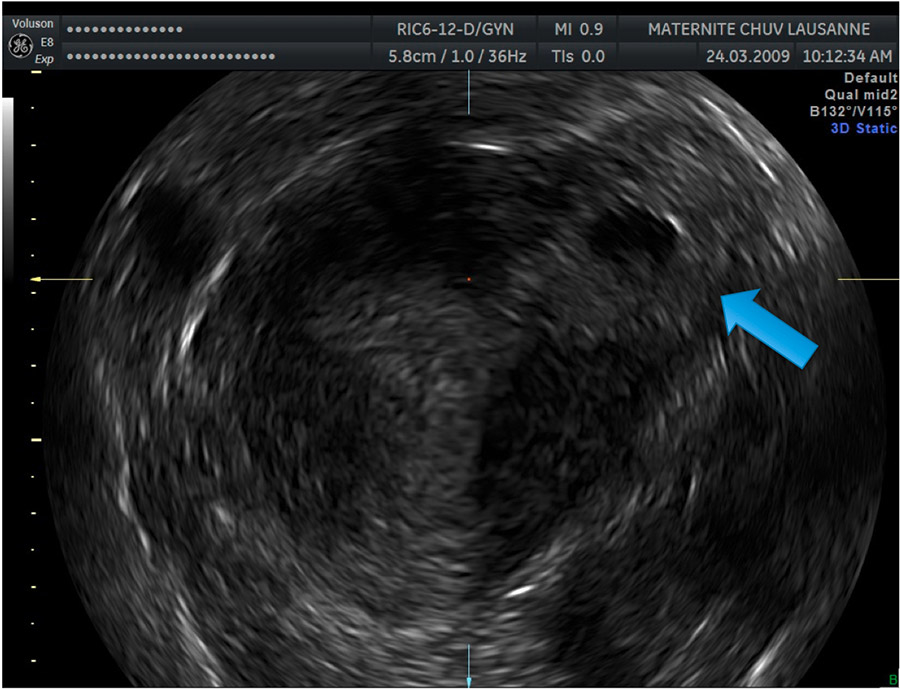

Figure 4

Image showing a left IP 3D reconstruction in a coronal sectional plane. The blue arrow indicates the lateral GS surrounded by a thin myometrial layer.

Progress in 3D TVUS makes this technique a good and precise diagnostic tool. In particular, the 3D reconstruction in a coronal sectional plane allows localisation of the GS in relation to the uterine cavity, therefore helping in differentiating the IP from an angular pregnancy [11–13] (fig. 4).